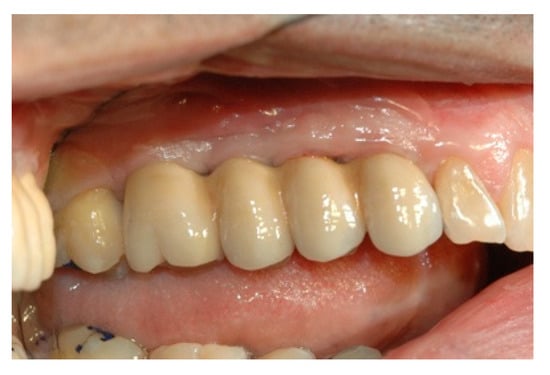

Form is the plastic image of function, and the waxings close to natural canons adhere to this concept. The functional investigation uses two practical detection methods: With the rapid facial arch, suitable for medium-complexity jobs, the positioning of the upper jaw is obtained. With the kinematic arc, the Bennet is detected in the intercondylar axis (hinge). In complex cases, the kinematic arch is used for the construction of the medium and long-term provisional, and with the diagnostic provisional the validity of the detections is verified and the TMJ behavior is checked. Prudence advises us to reduce the occlusal surfaces in order to reduce the lever arm on the implant. The modern provisional has many roles—it is the therapeutic and diagnostic name. It is in the implant prosthesis that it finds its main application, and is often underestimated (Figure 3).

The long-term diagnostic provisional is of enormous importance for the success of the final prosthesis. A design with good level characteristics must therefore be carried out: an axiographic investigation and a diagnostic wax-up on an individual articulator. In the search for the correct vertical dimension, the dentist can use the provisional to increase the vertical dimension; this method is based on the experience of the professional, who empirically determines the size. Alongside this, the radiologist and orthodontist determine on the basis angles and vertical dimension at different schools. The presence of any contractures determines a joint problem. During the medical history, the clinician will check the state of muscle tension, and a palpation to the muscles assigned to the occlusion will verify the pain. In the presence of problems at the A.T.M. before definitive rehabilitation, the clinician may decide to make small corrections to the occlusion; increase or decrease the vertical dimension; create guides; and bring the condyles back to the centric position, guiding the occlusion with an incisive canine guide and eliminating harmful contacts. The provisional diagnostic is responsible for the investigation and the functional verification before the definitive rehabilitation that will duplicate and follow it. Only after having ascertained the correct biomechanical functioning of the temporary bridge can the final ceramic metal girder of the occlusal line be realized [32,33].

Figure 3. Occlusal line and test on articulator.